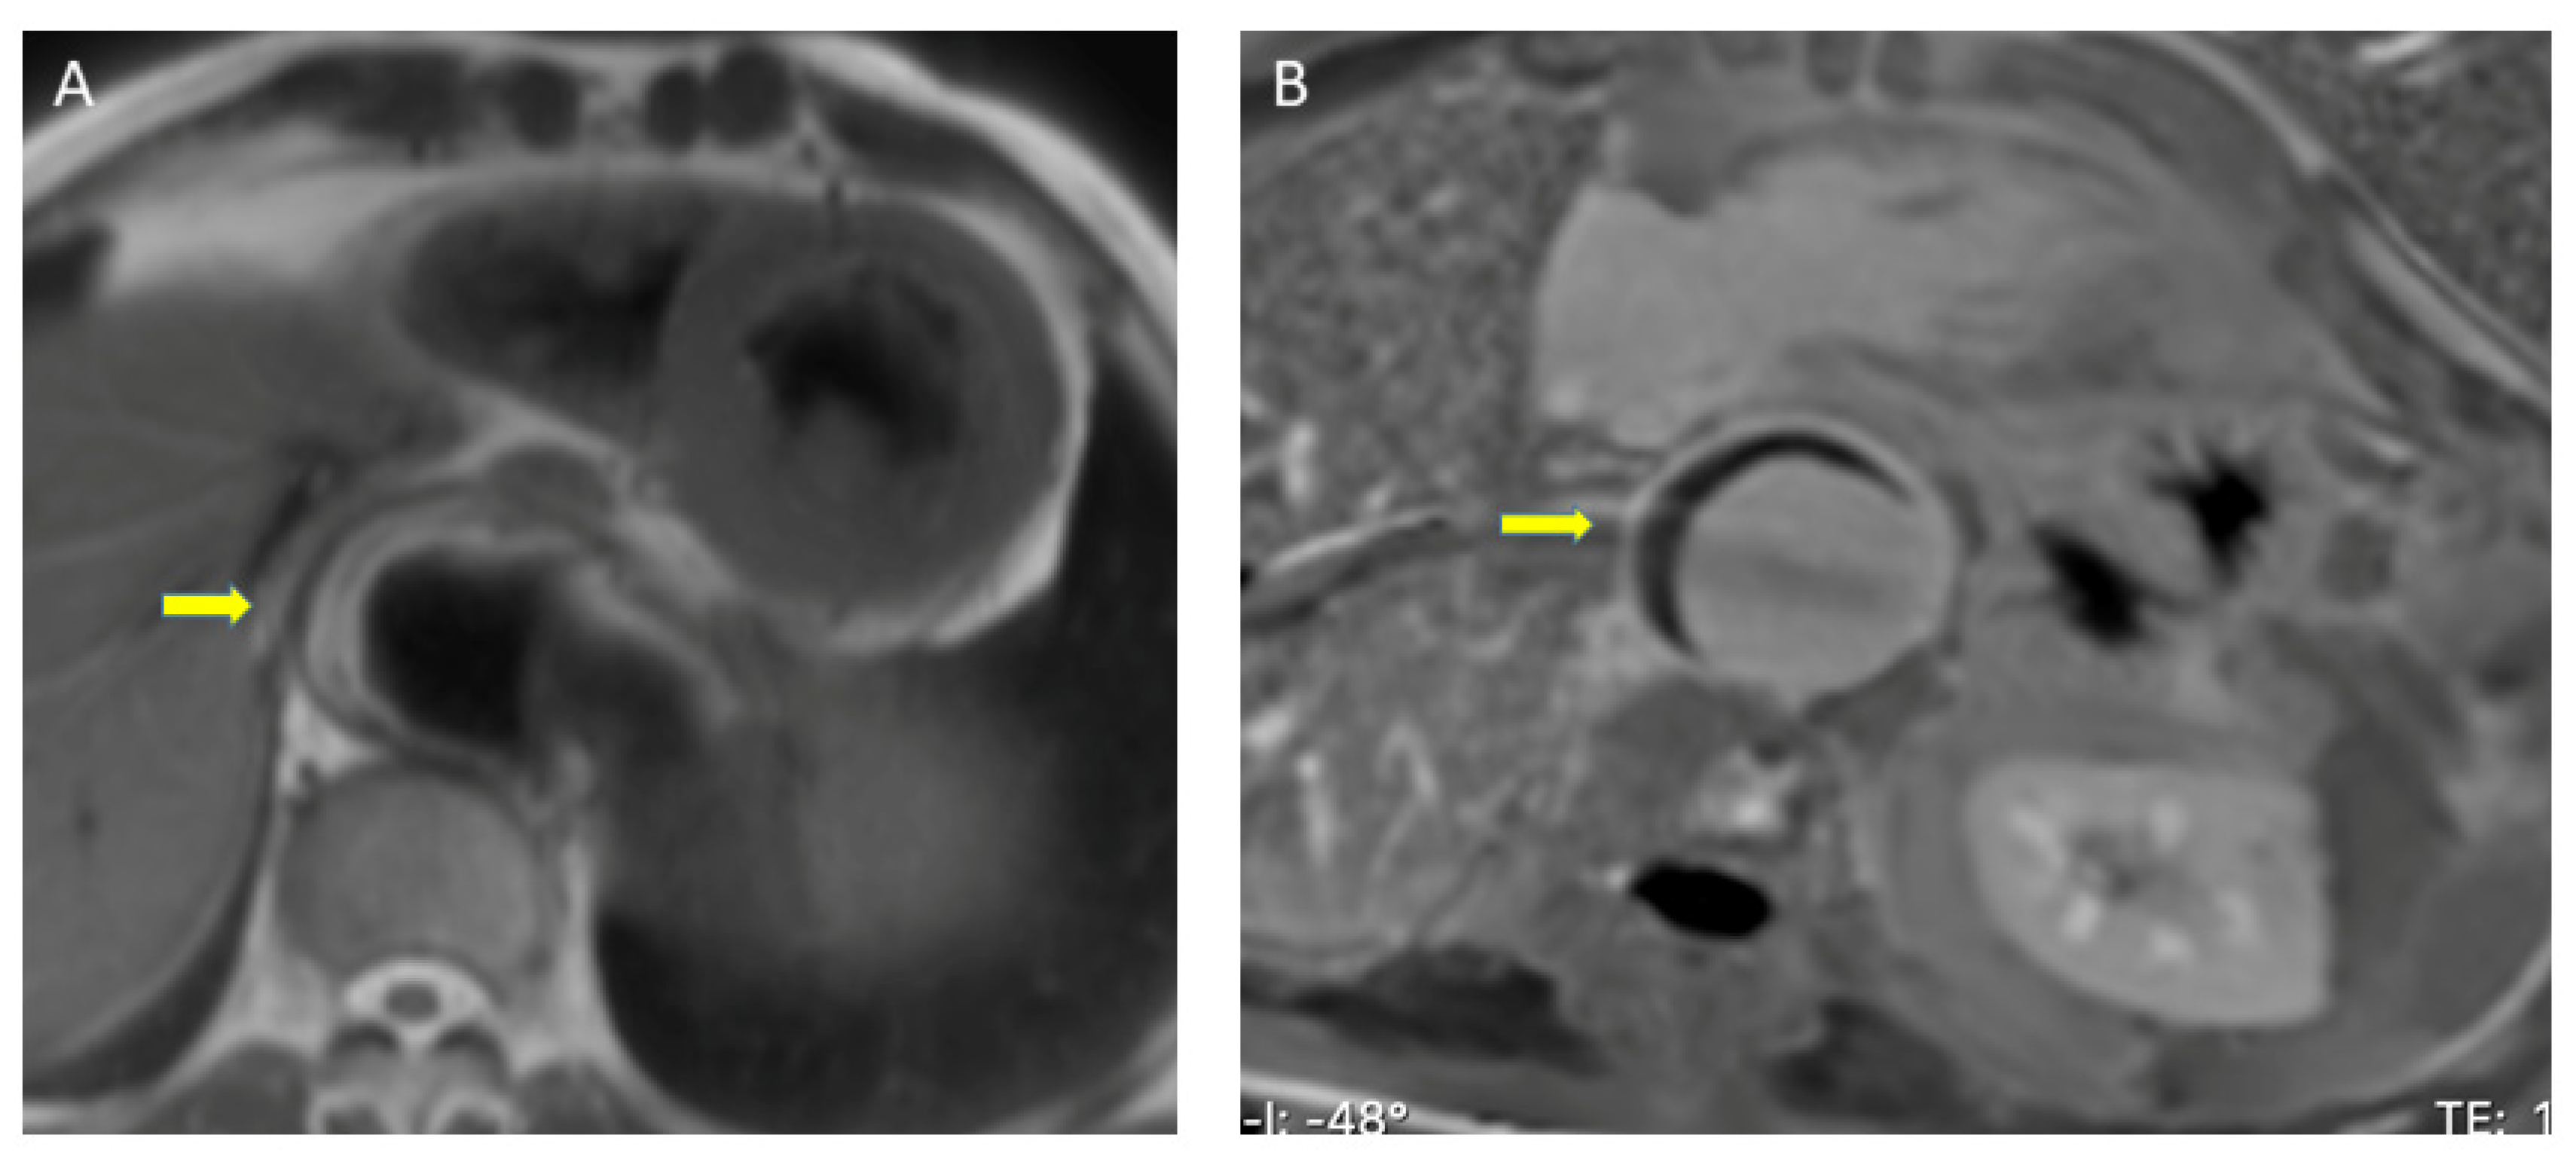

Breath-hold ECG-gated fast spin echo images acquired with T1 and T2 weighting are used to assess aortic calibre, aortic wall thickness, and aortic wall signal change. These are acquired as contiguous transverse sections from the apexes to the infrarenal abdominal aorta and also as sections paralleling the long axis of the aortic arch. On MRI, the spin-echo black blood images of an IMH show a crescent-shaped area of eccentric thickening, and exhibit the expected signal characteristics associated with the transition of hemorrhage from deoxyhemoglobin (low T1 and T2) in the hyperacute stage to intracellular methemoglobin (high T1, intermediate T2) in the subacute stage and extracellular methemoglobin (high T1 and T2) in the late stage of IMH (Figure 4A).

Figure 4.

Magnetic resonance imaging assessment of intramural hematoma (arrows). (A) Spin-Echo sequence. The eccentric thickening of the aortic wall has a high T1 signal, eliminating the possibility that it is an acute stage. (B) Late gadolinium- enhancement sequence. Aortic eccentric wall thickening with no mural enhancement, suggestive of intramural hematoma.

A small study suggested three magnetic resonance angiography (MRA) parameters to distinguish IMH from type B dissection: (1) no visualized entry tear, (2) no contrast uptake in aortic lesion on first pass angiography, and (3) no contrast uptake in the aortic lesion on the equilibrium phase T1-weighted sequence [50]. In addition, post-gadolinium sequences are useful to discriminate between aortitis and IMH: mural enhancement is not an expected feature of IMH [51,52] (Figure 4B).